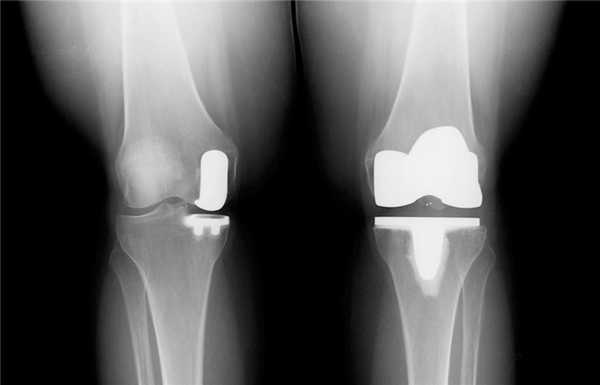

Две техники операции у одного пациента.

Одномыщелковая замена сустава на рентгене.

Сравнение двух типов операций.

Одномыщелковое протезирование подразумевает срок службы небиологического устройства максимум 7 лет. Тотальное замещение предусматривает время службы вживленного механизма от 15 лет. Ревизионное переносится сложнее, а риск инфекции и других негативных явлений почти в 2 раза выше, чем после первичной операции.